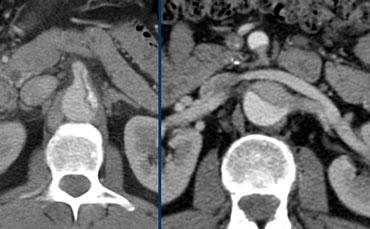

Trái: Bóc tách tiếp tục vào thân tạng cho thấy lòng giả lớn hơn, đóng góp đáng kể vào tưới máu tạng. Phải: Liên quan đến SMA và động mạch thận, minh họa nguyên nhân có thể gây thiếu tưới máu tạng.

Bóc tách vào các động mạch bụng

Dòng chảy của thân tạng, SMA và động mạch thận phải thường xuất phát từ lòng thật.

Dòng chảy của động mạch thận trái chủ yếu xuất phát từ lòng giả.

Tưới máu kém đến các cơ quan đích có thể do 2